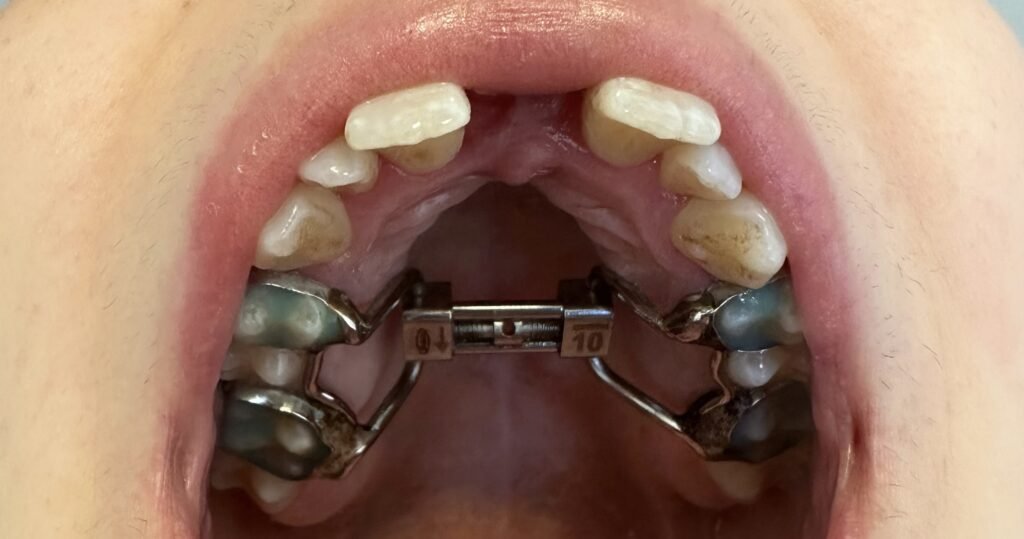

A cirurgia de expansão maxilar, após a adolescência, é realizada sob anestesia geral. O procedimento envolve a aplicação de um dispositivo chamado expansor palatino, que é colocado no céu da boca do paciente, dias antes da cirurgia, pelo seu Médico Dentista. Durante a cirurgia é feita uma osteotomia (corte) da sutura palatina que irá permitir a expansão do maxilar. Este expansor é ajustado gradualmente ao longo de alguns dias para separar as duas metades do maxilar, promovendo o alargamento ósseo.

Antes, durante e depois da expansão maxilar cirurgicamente assistida